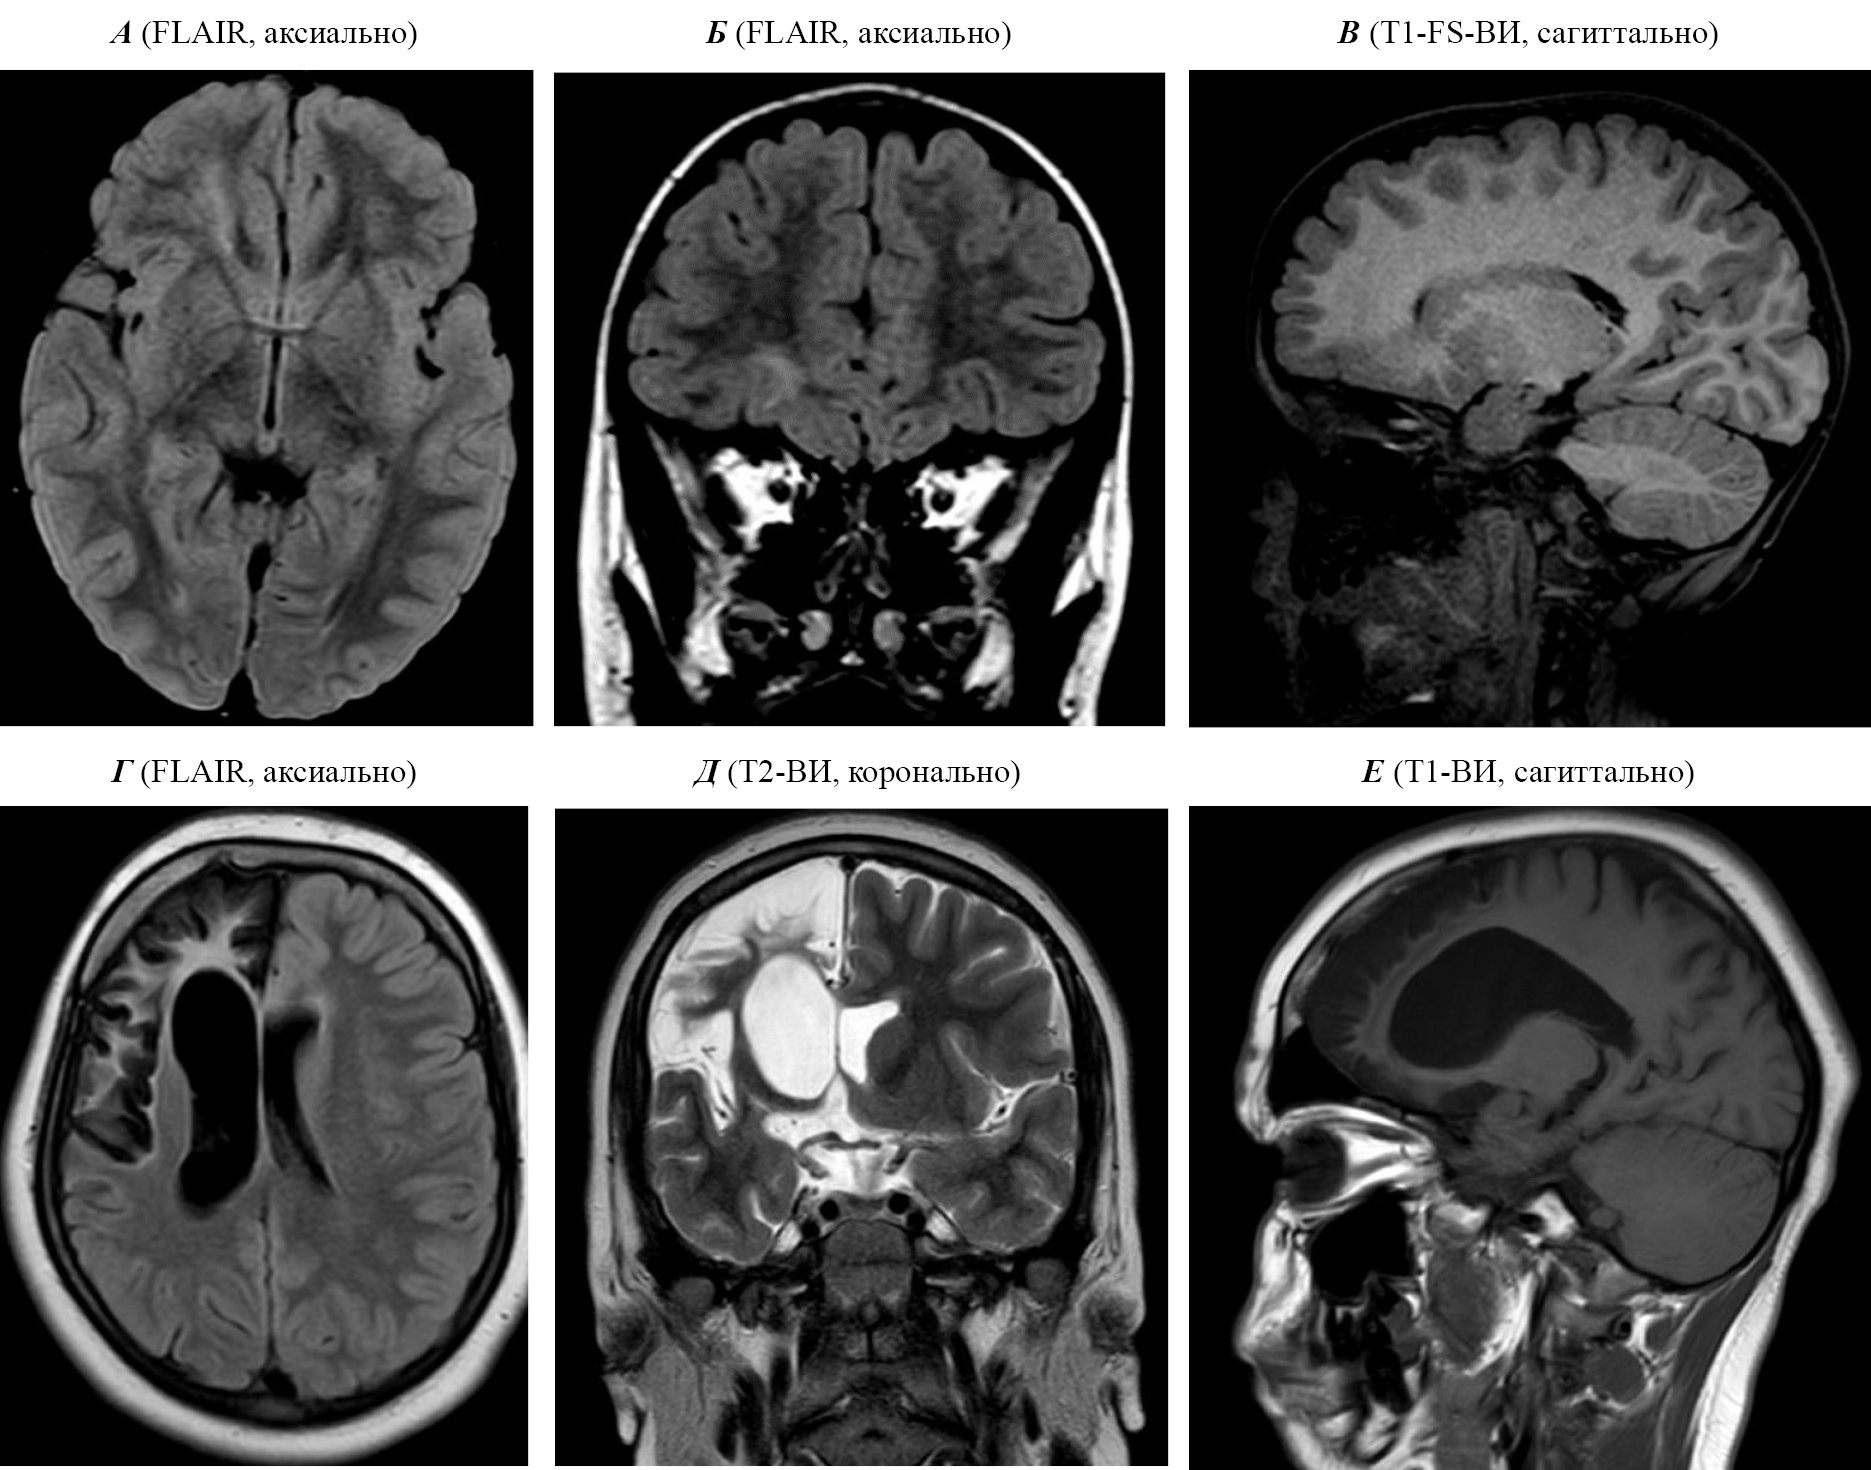

В ФГБУ «Детский научно-клинический центр инфекционных болезней Федерального медико-биологического агентства» России (ФГБУ ДНКЦИБ ФМБА России) внедрен современный подход к клинически значимым диагностическим методам у детей с различными формами нейроинфекций. Так, в остром периоде нейроинфекций в зависимости от ее формы применяются электрофизиологические, ультразвуковые и компьютерно-томографические методики. Нами, в частности, установлено, что ультразвуковое исследование диаметра оболочки зрительного нерва может применяться для мониторинга внутричерепной гипертензии у детей с критическими состояниями на фоне нейроинфекций. Диаметр оболочки зрительного нерва у пациентов детского возраста в критических состояниях варьирует от 5,2 до 6,8 мм, средний размер 5,8 ± 0,5 мм. У всех пациентов с нейроинфекциями, находящихся в критическом состоянии в отделении реанимации и интенсивной терапии, наблюдается расширение оболочки зрительного нерва по сравнению с нормой: типичные изменения представлены на рис. 1.

Рис. 1. Сонограмма пациента с повышением внутричерепного давления. Диаметр расширенной оболочки зрительного нерва 5,8 мм

На фоне улучшения состояния пациентов наблюдается уменьшение диаметра диска зрительного нерва в среднем на 5,2 ± 0,2 мм (p < 0,05). Наблюдаемое уменьшение диаметра коррелирует с клиническим улучшением (повышением уровня сознания, уменьшением выраженности общемозговой и инфекционной симптоматики). Таким образом, у детей с критическим состоянием на фоне инфекционных заболеваний выявляемые ультразвуковые изменения допустимо соотносить с клинической картиной. Для этих целей возможно использование портативных, простых в применении и анализе получаемых результатов аппаратов ультразвуковой диагностики. Безопасность методики ультразвукового исследования зрительных нервов в педиатрической практике сомнению не подвергается, в том числе при использовании у детей в условиях отделения реанимации и интенсивной терапии [7, 8].